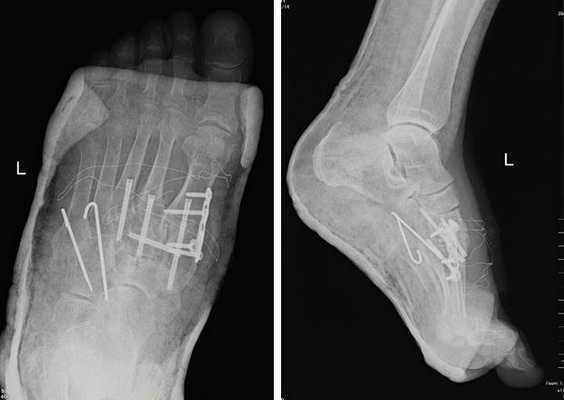

После осмотра в отделении ортопедии №2 ГКБ №13 принято решение о проведении операции – открытому устранению вывиха, артродезе 1-2-3 плюсне-клиновидных суставов, 1 межклиновидного сустава при помощи винтов и пластины, трансартикулярной фиксации спицами 4-5 плюсне-клиновидных суставов.

![вывих в суставе Лисфранка операция]()

Первым этапом выполняется удаление костно-хрящевых экзостозов и рубцовых тканей из области всего сустава Лисфранка. После этого дистальный отдел стопы приобретает мобильность, достаточную для восстановления нормальной анатомии. Остатки суставного хряща полностью удаляются с 1-2-3 плюсне-клиновидных суставов, 1 межклиновидного сустава при помощи долота, осцилляторной пилы, кусачек Люэра, острой ложки Фолькмана. Для репозиции используются костные цапки.

![переломовывих в суставе Лисфранка операция]()

Вершиной, ключом, блокирующим клином – в общем главной частью сустава Лисфранка является 2 плюсне-клиновидный сустав. По этой причине мы предпочитаем начинать фиксацию именно с него. Для артродеза используем винты с направленной в разные стороны резьбой FT Arthrex диаметром 4 мм. Они позволяют создать мощную межфрагментарную компрессию, а за счёт глубокой резьбы очень надёжно фиксируются в кости.

![винты для артродеза сустава лисфранка]()

После восстановления 2 луча выполняем артродез межклиновидного сустава и 1 плюсне-клиновидного сустава. Учитывая что основная нагрузка ложится на 1 луч, дополнительно стабилизируем его при помощи пластины.

![артродез сустава лисфранка]()

![вывих в суставе лисфранка рентген]()

В стационаре пациент находится первые 2 суток после операции. Это необходимо для купирования болевого синдрома, и контроля послеоперационной раны. На 3 сутки пациент выписывается домой в гипсовой лонгетной повязке, на костылях. На ногу наступать нельзя до 6 недль после операции. Послеоперационные швы снимаются через 2 недели, лонгетная повязка при этом может быть заменена на циркулярный обычный или пластиковый гипс или ортез.

![гипс после операции на суставе лисфранка]()

В итоге через 3 месяца мы получаем стабильную, безболезненную, опороспособную конечность. Через 6 месяцев можно начать спортивные нагрузки.